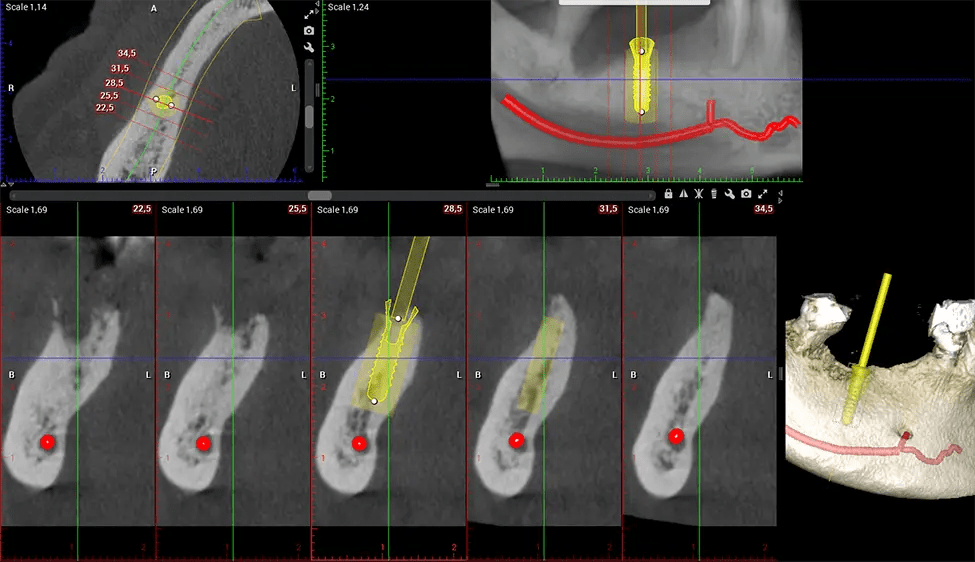

When paired with extractions, dental implant placement, or bone grafting, CBCT technology can provide you with a quicker and much more comfortable experience. This is because the 3D image provides a more detailed picture of your entire oral cavity, allowing your dentist to walk you through each step of the process before it occurs. This often helps patients feel more prepared and comfortable overall, especially if they have had a traumatic experience with past dental treatments.

After the scanning process, the captured X-ray images are processed by the CBCT software, which applies algorithms to reconstruct a detailed 3D image of the scanned area. The software compiles these individual X-ray images and creates a digital 3D representation of the patient’s anatomy. The reconstructed 3D CBCT image can be viewed and analyzed by the dentist or radiologist. This image can be manipulated, rotated, and zoomed in or out to examine specific structures and evaluate the patient’s condition.

Oral and Maxillofacial Surgeon Complex oral surgeries, orthognathic (jaw) surgery, and removal of impacted teeth. Offers precise, three-dimensional visualization of the skull, jaw, and craniocervical junction to enhance diagnostic accuracy and minimize surgical risks.